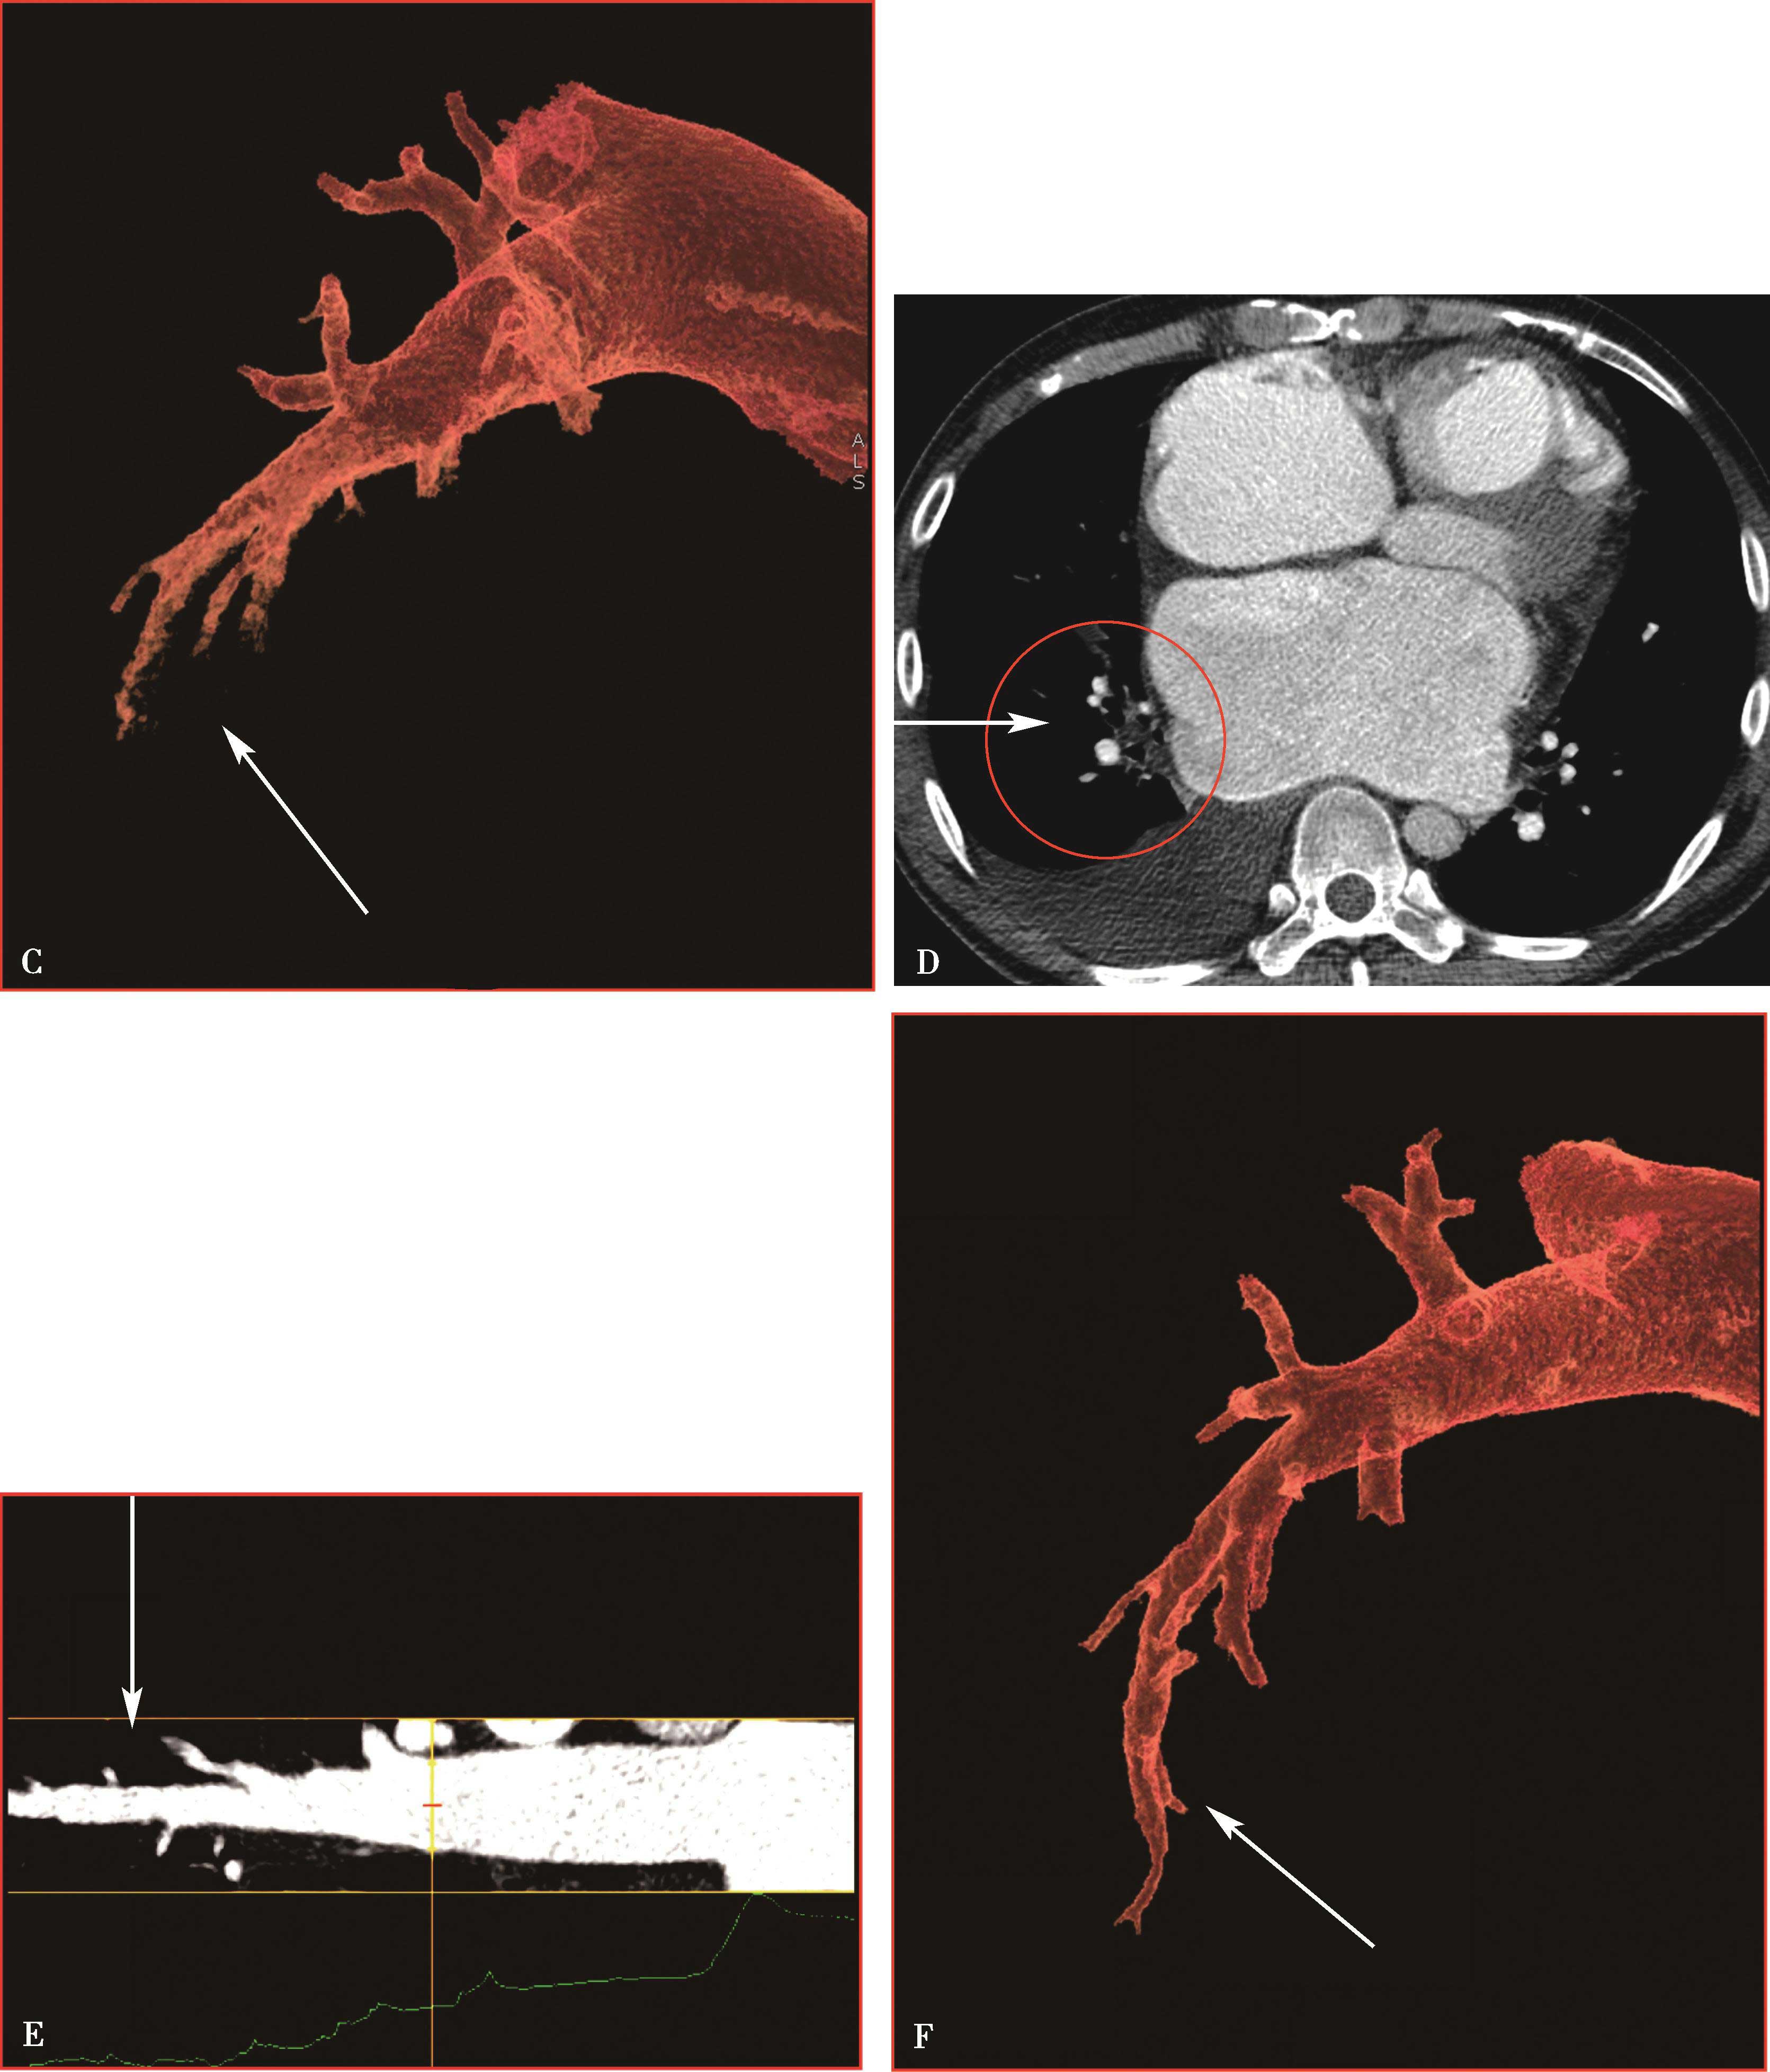

图8-1-5 CTPA两期扫描应用:患者,男,37岁,二尖瓣狭窄,肺循环高压,怀疑肺栓塞。第一期右肺下叶基底段对比剂充盈不充分(ABC↑);第二期充盈充分(DEF↑),排除肺栓塞诊断

(二)双期扫描法(图8-1-5)

4.扫描采用的对比剂跟踪技术,监测层面设定在上腔静脉入右心房的层面,ROI定为上腔静脉,触发阈值定义为80~100HU。

5.当ROI的CT值达到阈值时启动增强扫描程序。实行双期扫描,第一期为肺动脉期,从肺尖扫描至膈肌,第二期为主动脉期,由膈肌扫描至肺尖,双期扫描范围一致。双期扫描的意义在于:①充分保证了对比剂团注时间与肺动脉CT数据采集时间的吻合;②肺动脉高压或/和右心功能不全循环时延长者,是一弥补措施;③多期观察可以辨别对比剂充盈不均造成的假象;④有利于对肺灌注的评价;⑤主动脉期可以兼顾观察左心系统的病变。